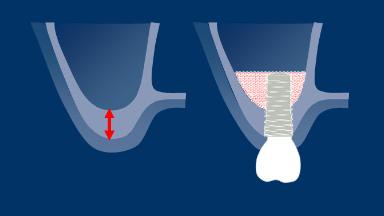

The site-specific assessments that will be discussed in this module are the restorative space and its characteristics, anatomical factors, and hard and soft tissue including any pathoses in the area.

- assess the restorative space and its characteristics